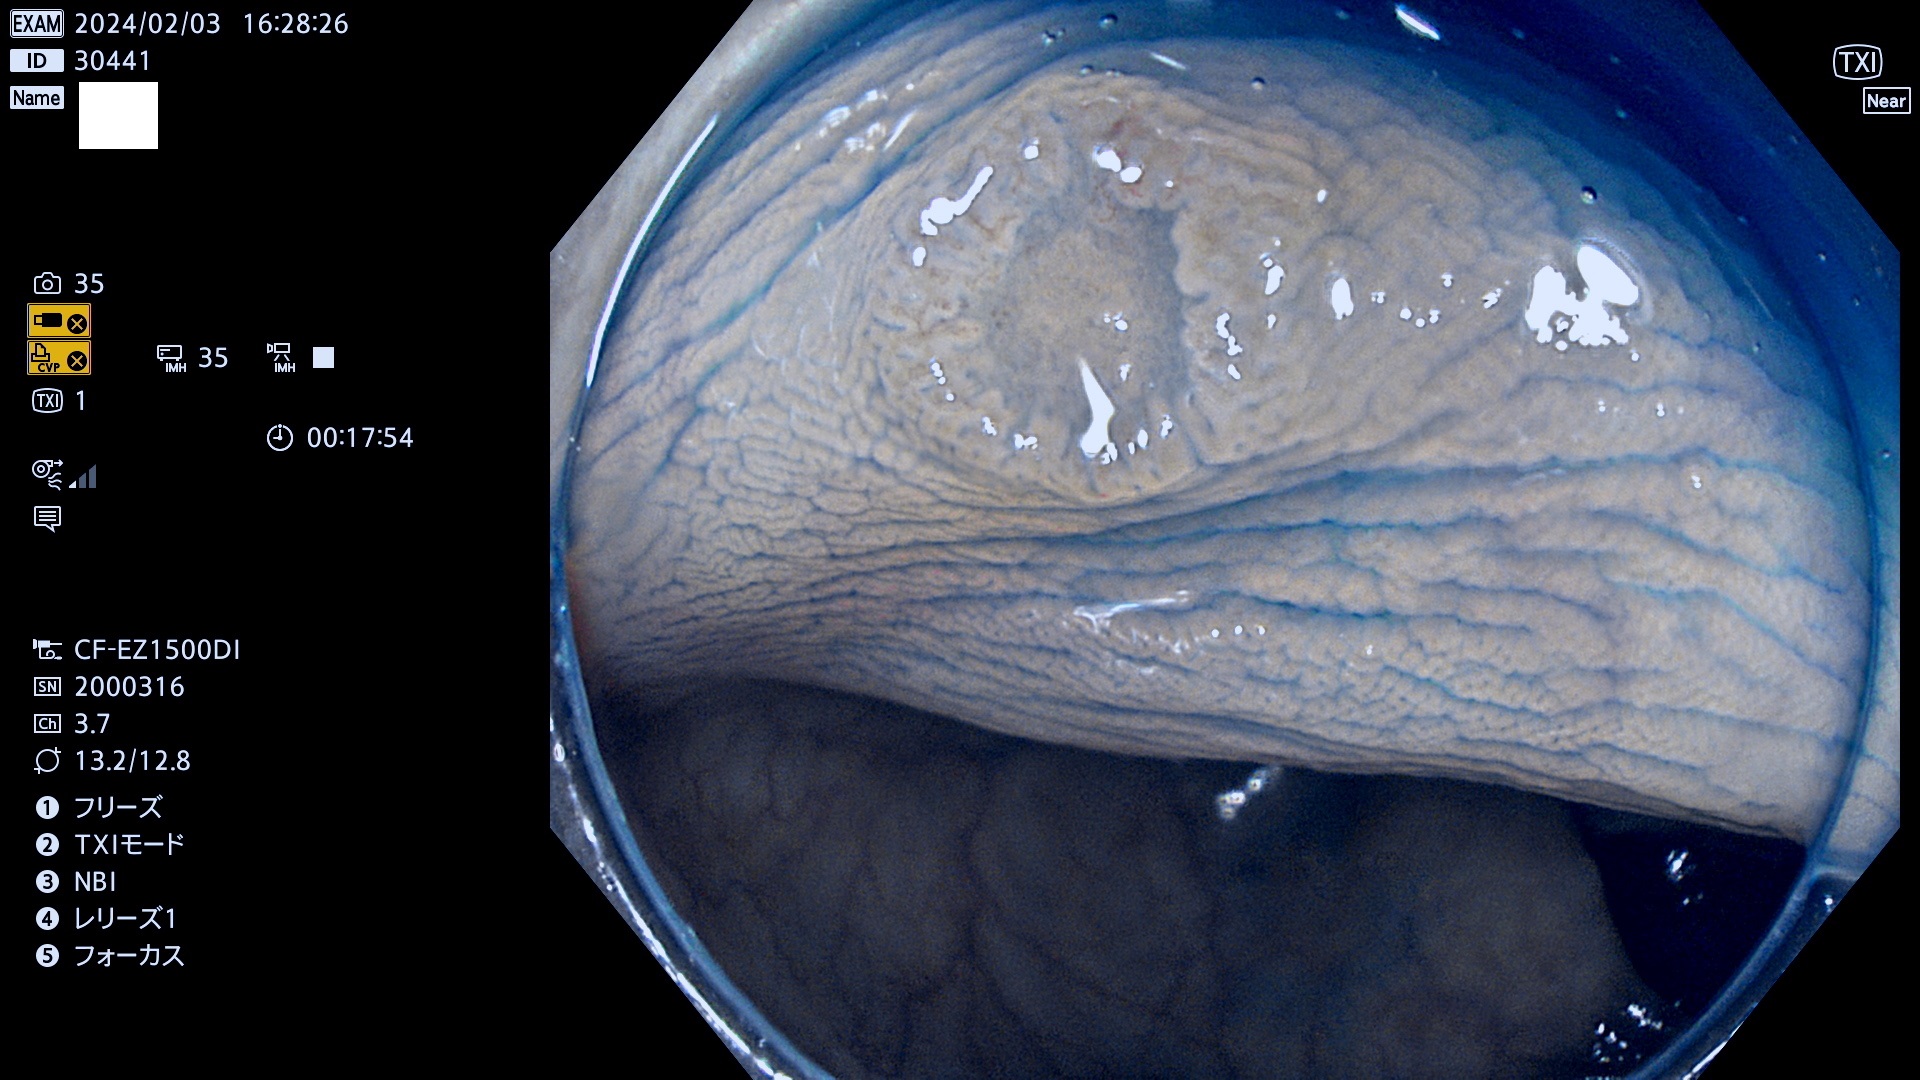

表面型腺腫(Flat Adenoma)の中で、完全に平坦な物をUb、陥凹している物をUcと呼びます。平坦隆起型(Ua)よりも、発見が難しく危険な病変です。

毎週の検査(木・金・土・日)に発見されたUb、Uc型・腺腫を、その週の日曜の夜にUPし1週間、提示します。

抽出の対象期間 2024年2月1日(木)〜2月4(日)の4日間(40件の検査)12件